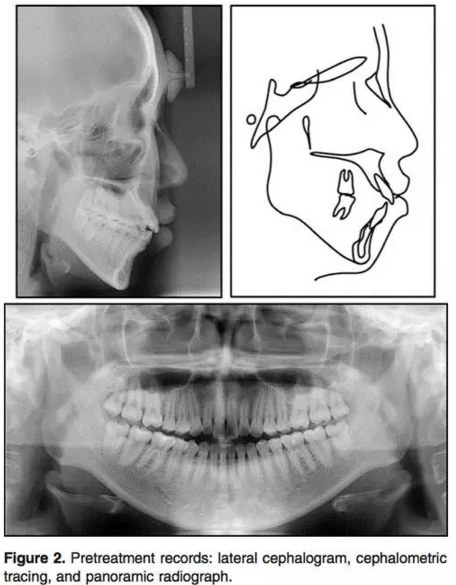

2.jpg

輔助檢查:側(cè)位片:骨性II類(ANB3.5°);下頜后縮(N per to Pog,-4.5°);高角(PFH/AFH, 59.5%; MP-FH, 32.7°)。上頜切牙輕微前突,下頜切牙突度正常(U1 to FH, 120.7°;IMPA, 90.0°)。上頜前后牙都垂直向發(fā)育過度(U1-PP, 36.9 mm; U6-PP, 27.9mm) 。上前牙在休息位時暴露量相對過量(U1 to stomion, 4.8 mm) 。咬合平面角正常(OP to FH, 12.8°)。此外,下頜垂直向高度也長于正常值 (L1 to mandibular plane, 47.7 mm; L6 to mandibular plane, 37.0 mm;Table 1) 。